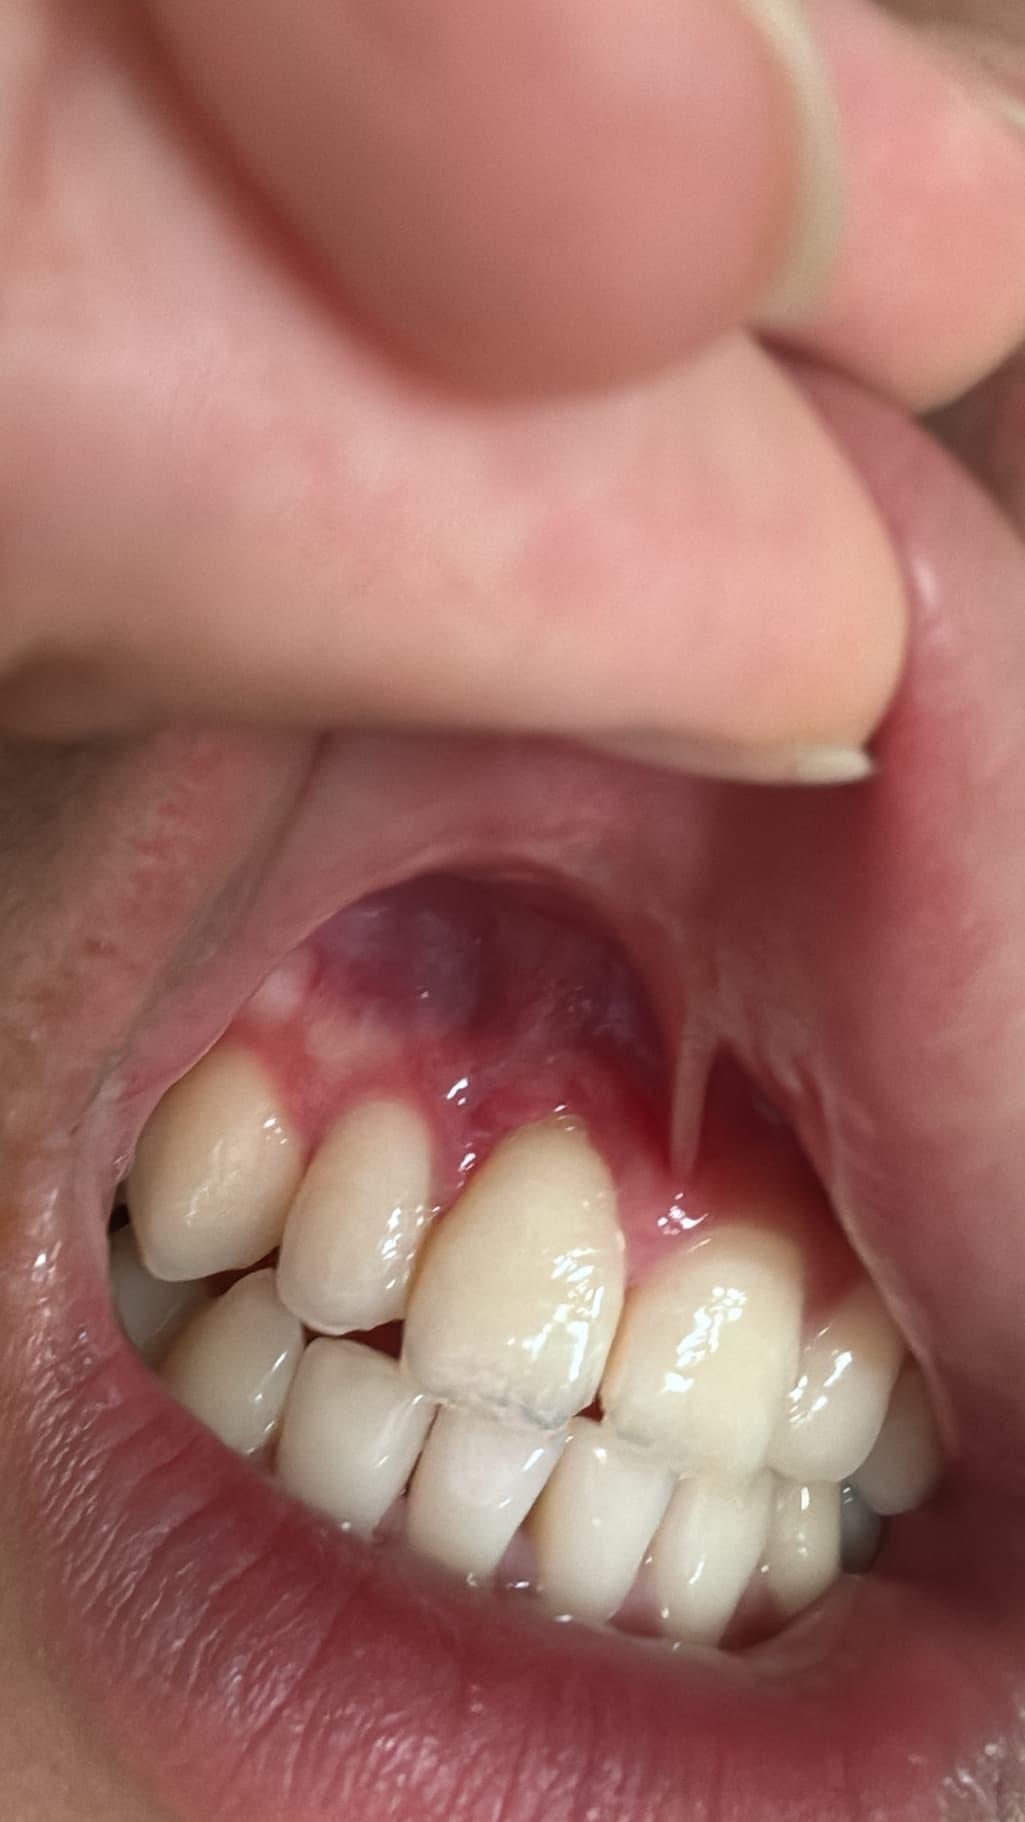

잇몸 절개 수술하고 2주정도 됐는데 잘 회복되고 있나요?

잇몸 절개 수술하고 2주 정도 지났는데 잘 회복되고 있나요? 그리고 이제 담배 펴도 아무문제 없을까요? 더이상 못참을거같아요..

사진상으로 잇몸이 잘 아물고 있는거 같습니다. 2주 정도 지낫다면 흡연을 하셔도 문제가 되진 않을것같습니다.

사진으로 봤을 때 잇몸은 잘 아물고 있는 것으로 보입니다. 흡연은 잇몸이 치유되는 것을 늦출 수 있기 때문에 피지 않는 것이 좋습니다.

사진상으로는 특별히 문제가 보이지는 않습니다. 흡연은 2주정도 지나셨다면 해도 됩니다.

절개 부위가 어느정도 아물긴 했으나 전부 다 아물진 않았습니다. 흡연은 가급적 삼가는 것이 좋겠습니다